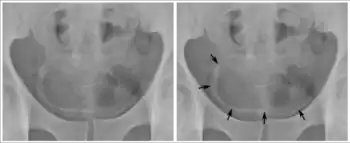

The bladder is a hollow organ in humans and other vertebrates that stores urine from the kidneys before disposal by urination. In humans, the bladder is a distensible organ that sits on the pelvic floor. Urine enters the bladder via the ureters and exits via the urethra. The typical adult human bladder will hold between 300 and 500 ml (10.14 and 16.91 fl oz) before the urge to empty occurs, but can hold considerably more.[1][2]

In humans, the bladder is a hollow muscular organ situated at the base of the pelvis. In gross anatomy, the bladder can be divided into a broad fundus (base), a body, an apex, and a neck.[3] The apex (also called the vertex) is directed forward toward the upper part of the pubic symphysis, and from there the median umbilical ligament continues upward on the back of the anterior abdominal wall to the umbilicus. The peritoneum is carried by it from the apex on to the abdominal wall to form the middle umbilical fold. The neck of the bladder is the area at the base of the trigone that surrounds the internal urethral orifice that leads to the urethra.[3] In males, the neck of the urinary bladder is next to the prostate gland.

The bladder has three openings. The two ureters enter the bladder at ureteric orifices, and the urethra enters at the trigone of the bladder. These ureteric openings have mucosal flaps in front of them that act as valves in preventing the backflow of urine into the ureters,[4] known as vesicoureteral reflux. Between the two ureteric openings is a raised area of tissue called the interureteric crest.[3] This makes the upper boundary of the trigone. The trigone is an area of smooth muscle that forms the floor of the bladder above the urethra.[5] It is an area of smooth tissue for the easy flow of urine into and from this part of the bladder - in contrast to the irregular surface formed by the rugae.

The walls of the bladder have a series of ridges, thick mucosal folds known as rugae that allow for the expansion of the bladder. The detrusor muscle is the muscular layer of the wall made of smooth muscle fibers arranged in spiral, longitudinal, and circular bundles.[6] The detrusor muscle is able to change its length. It can also contract for a long time whilst voiding, and it stays relaxed whilst the bladder is filling.[7] The wall of the urinary bladder is normally 3–5 mm thick.[8] When well distended, the wall is normally less than 3 mm.

The bladder is located below the peritoneal cavity near the pelvic floor and behind the pubic symphysis. In males, it lies in front of the rectum, separated by the recto-vesical pouch, and is supported by fibres of the levator ani and of the prostate gland. In females, it lies in front of the uterus, separated by the vesico-uterine pouch, and is supported by the elevator ani and the upper part of the vagina.[8]

Urine, excreted by the kidneys, collects in the bladder because of drainage from two ureters, before disposal by urination (micturition).[11] Urine leaves the bladder via the urethra, a single muscular tube ending in an opening called the urinary meatus, where it exits the body.[9] Urination involves coordinated muscle changes involving a reflex based in the spine, with higher inputs from the brain.[11] During urination, the detrusor muscle contracts, and the external urinary sphincter and muscles of the perineum relax, allowing urine to pass through the urethra and out of the body.[11]